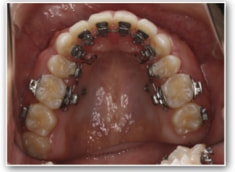

叢生+左下1番先天欠如ケース

治療法:裏側の矯正(リンガルブラケット:舌側矯正)

治療開始1年後